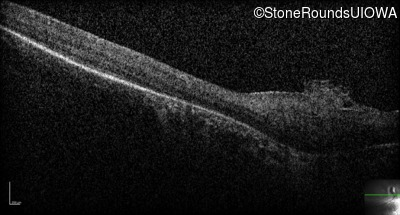

Optical Coherence Tomography - Right - No Light Perception

Exemplar / OCT Stack